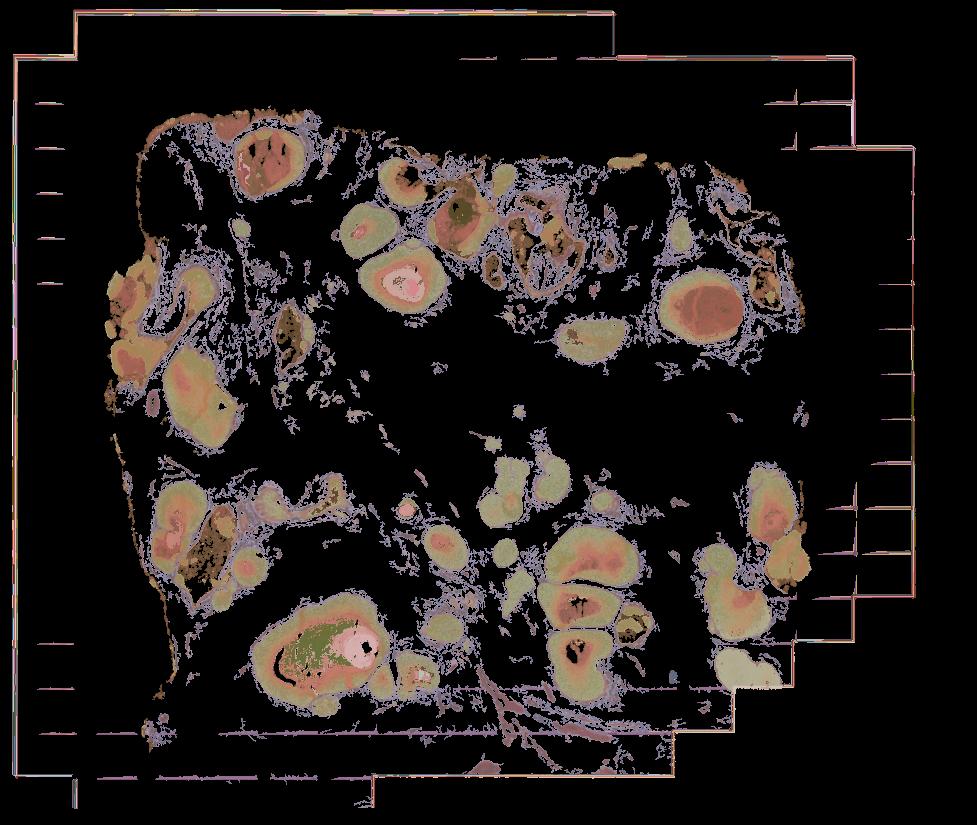

Atlas: Washington University

Breast cancer (BC) is defined by distinct molecular subtypes with different cells of origin. The transcriptional networks that characterize the subtype-specific tumor-normal lineages are not established. In this work, we applied bulk, single-cell and single-nucleus multi-omic techniques as well as spatial transcriptomics and multiplex imaging on 61 samples from 37 patients with BC to show characteristic links in gene expression and chromatin accessibility between BC subtypes and their putative cells of origin. Regulatory network analysis of transcription factors underscored the importance of BHLHE40 in luminal BC and luminal mature cells and KLF5 in basal-like tumors and luminal progenitor cells. Furthermore, we identify key genes defining the basal-like (SOX6 and KCNQ3) and luminal A/B (FAM155A and LRP1B) lineages. Exhausted CTLA4-expressing CD8+ T cells were enriched in basal-like BC, suggesting an altered means of immune dysfunction. These findings demonstrate analysis of paired transcription and chromatin accessibility at the single-cell level is a powerful tool for investigating cancer lineage and highlight transcriptional networks that define basal and luminal BC lineages.